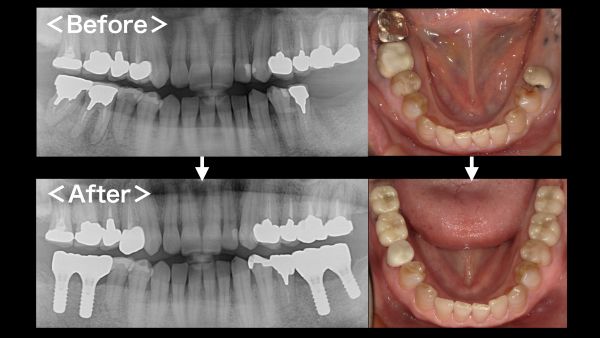

こちらが初診時のレントゲン写真となります。

左下6・7番目の歯が抜歯をされ、欠損している状態でした。

こちらが被せ物が入った後のレントゲン写真になります。